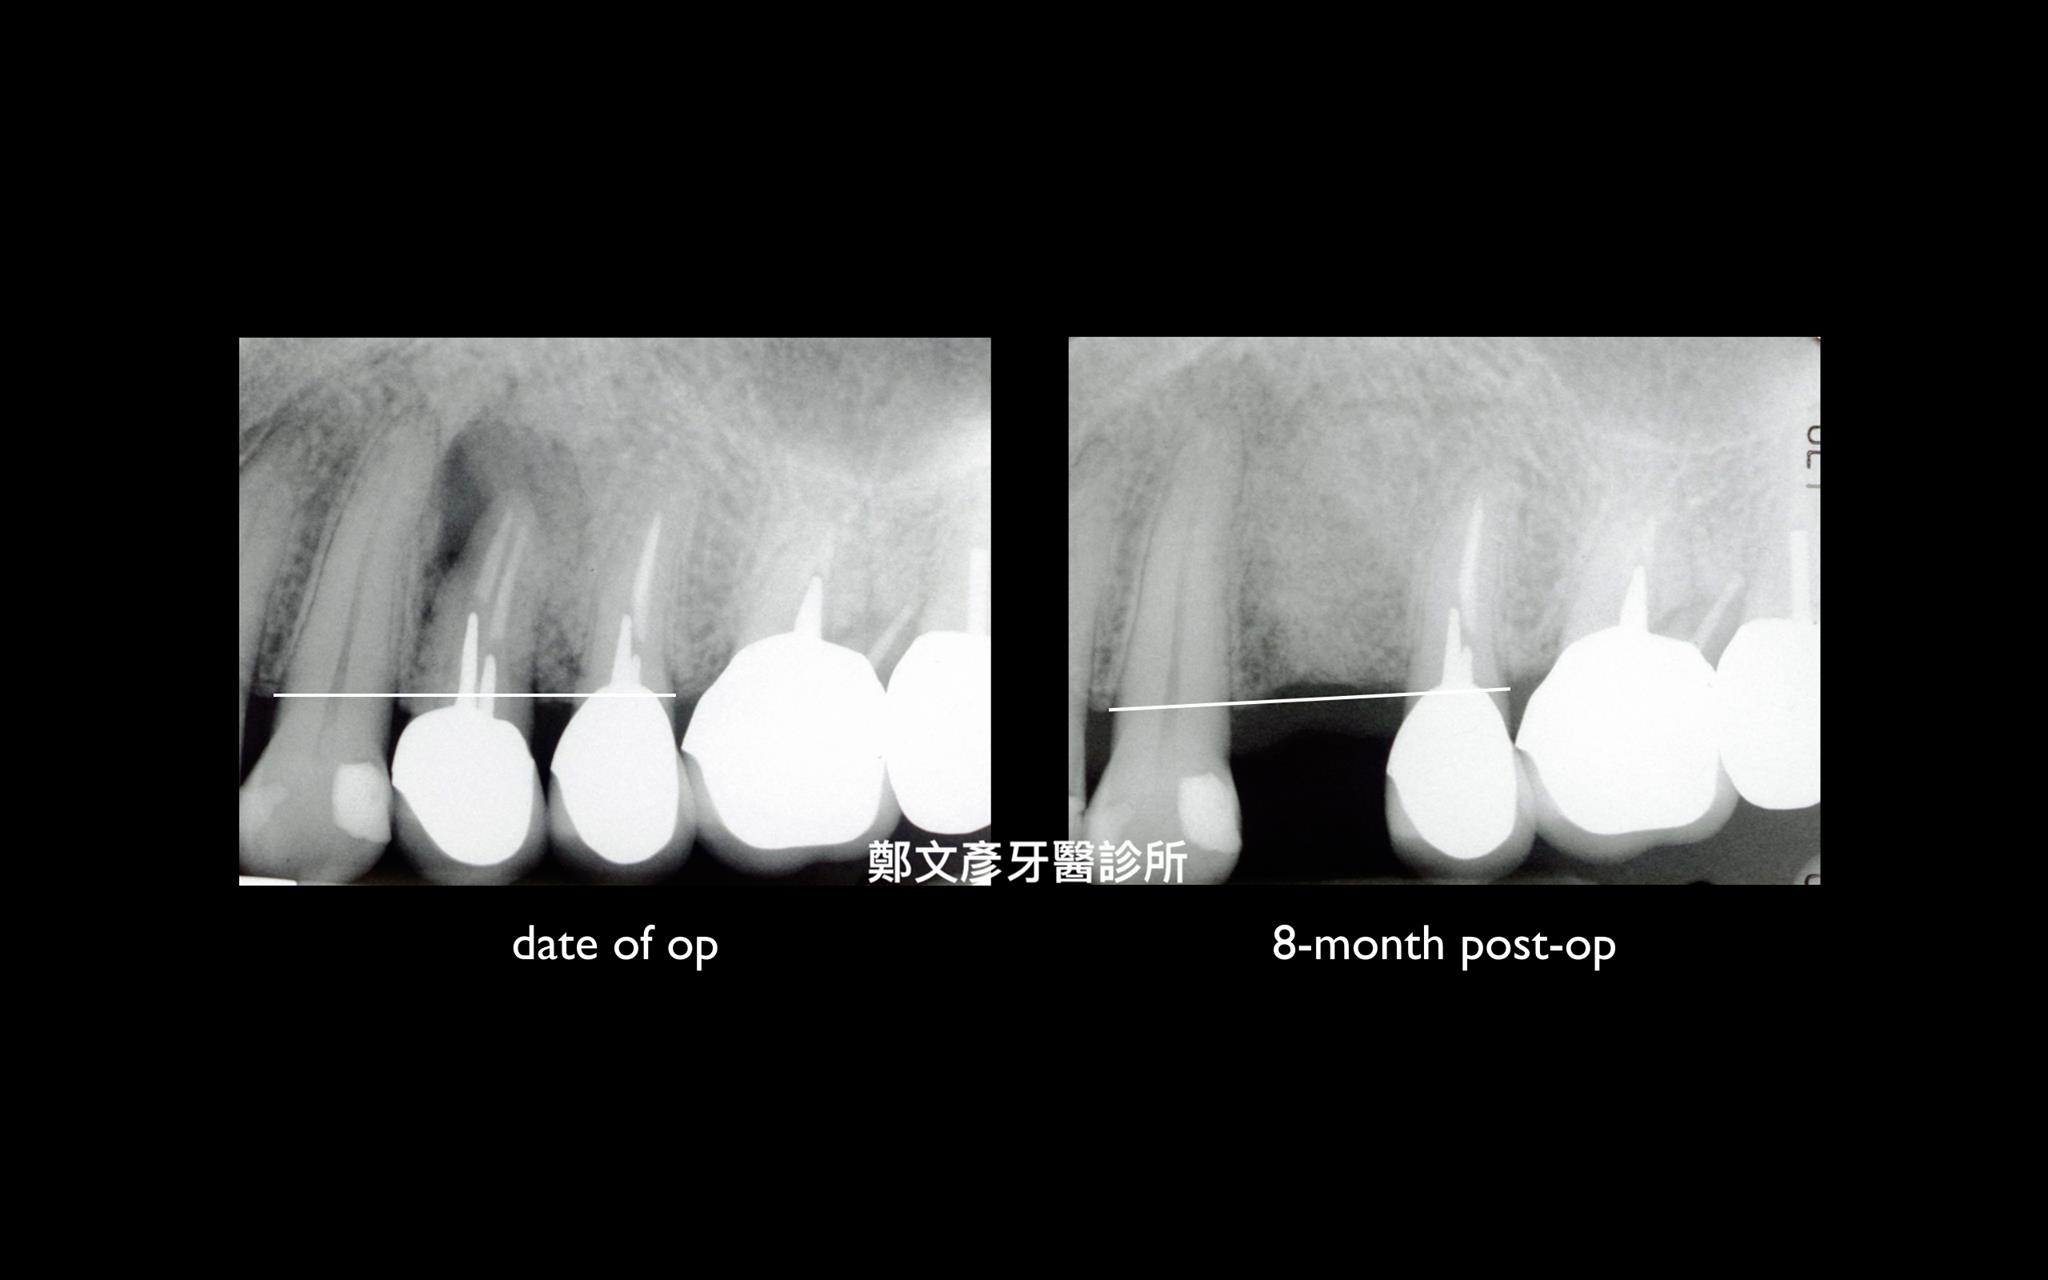

3. Role of granulation tissue in socket preservation

Role of granulation tissue in socket preservation